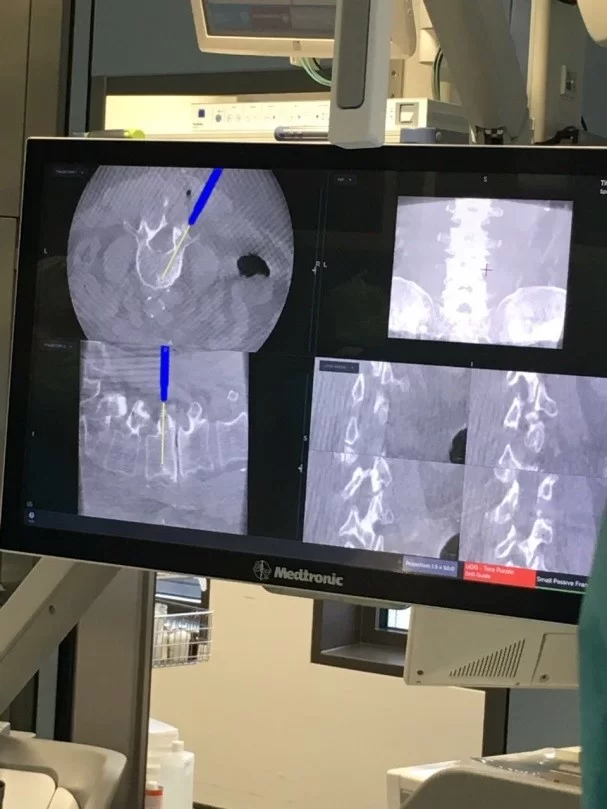

Σημαντική βοήθεια για τη διενέργεια τέτοιων επεμβάσεων αποτελεί η τρισδιάστατη νευροπλοήγηση της σπονδυλικής στήλης, η οποία επιτρέπει τα υλικά να τοποθετούνται με ακρίβεια χιλιοστού (Εικόνα 1 και 2).